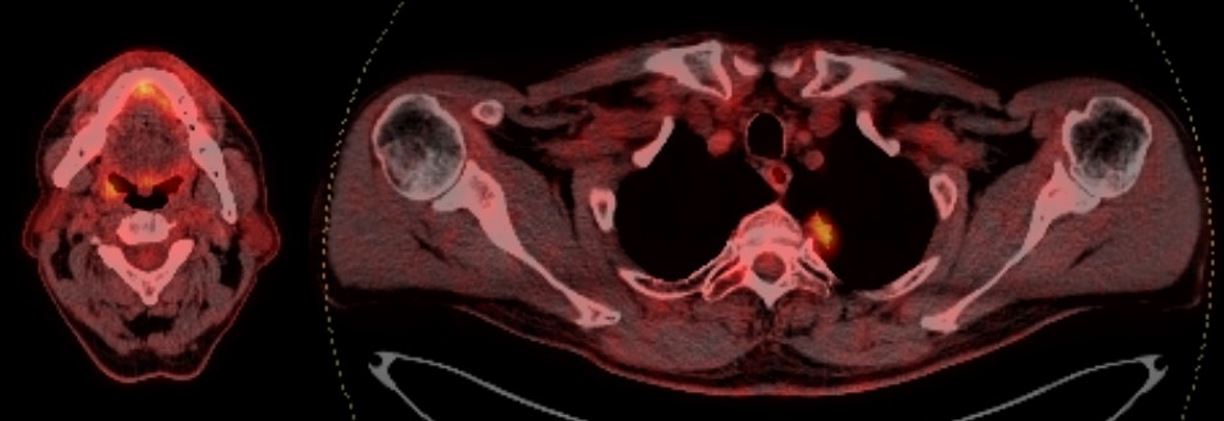

3. Рис. 3. МСКТ органов грудной клетки (гиповаскулярное солидное образование со спикулами в проекции верхушки левого легкого, широко прилежащее к плевре). Примечание: рисунок выполнен авторами | |